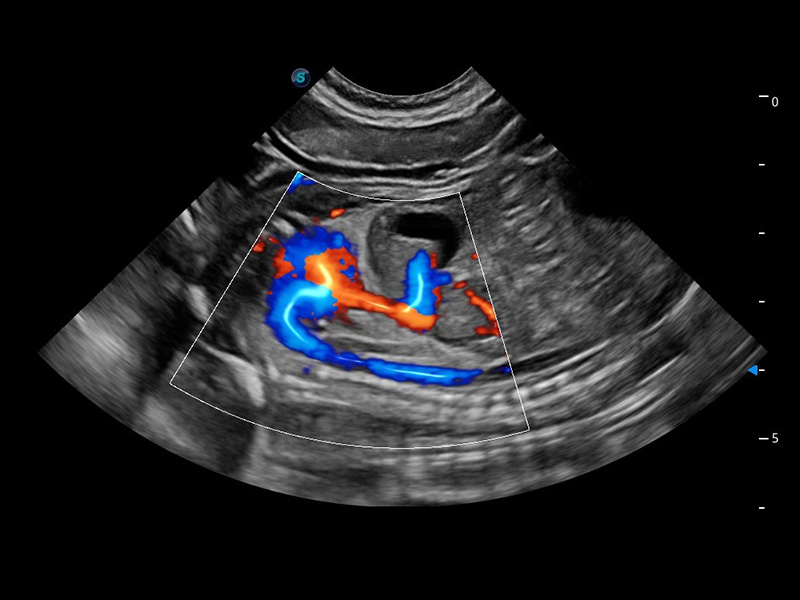

ProPet 60 作为一款高端台式动物超声设备,为动物医生的日常诊断提供了一系列贴合动物临床需求、解决临床实际问题的高级成像功能。凭借全系列高清探头,满足医生对腹部、心脏、生殖、浅表、肌骨等成像的所有需求,切实帮助您提升检查效率,提高诊断信心。

动物是人类最亲密的朋友和最值得信赖的伙伴。DB中国旗舰官方网站也一直致力于探索动物专用的超声影像解决方案。 全新推出的ProPet系列,是DB中国旗舰官方网站在动物超声影像智能化、专业化、精准化的一次跨越式革新。动物不能用言语来表述自己的不适,通过超声影像,ProPet系列搭建了动物医生与不同物种沟通的“桥梁”,为动物医生注入了“治愈之力”。